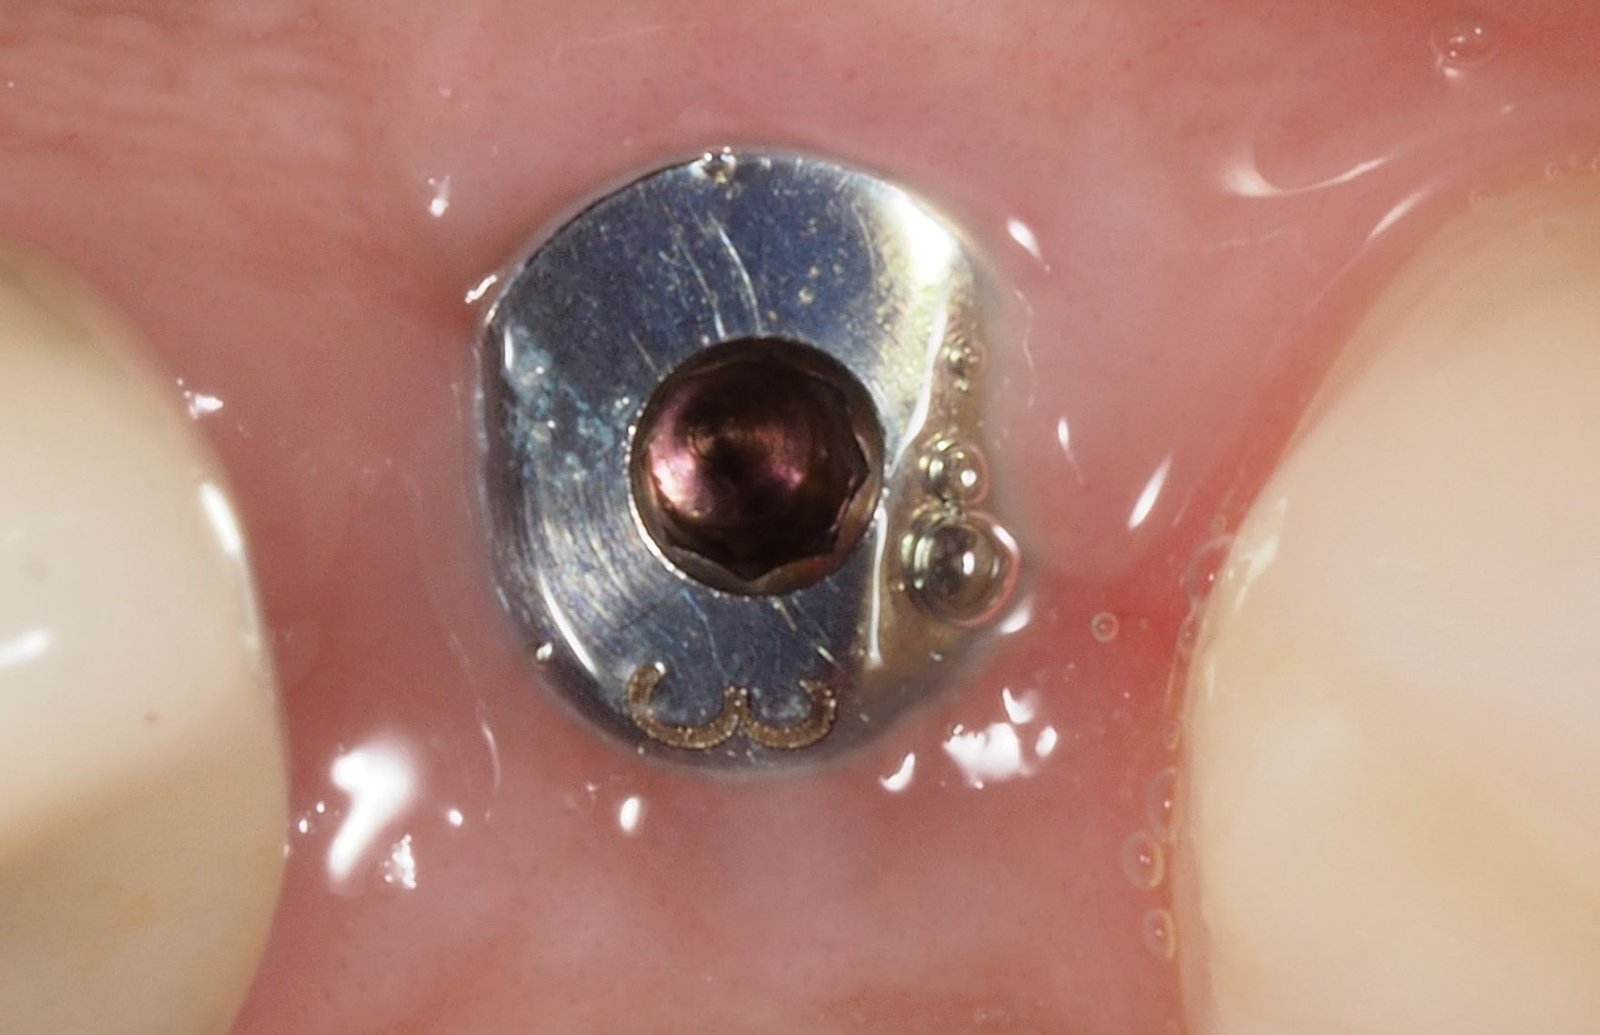

Hola, me ha venido para restaurar el 23. Es un implante tipo bone level pero no puedo quitar el tapón de cicatrización. No me vale el destornillador de 1.2 ni [...]

sabeis qué tipo de implante es? muchas gracias!